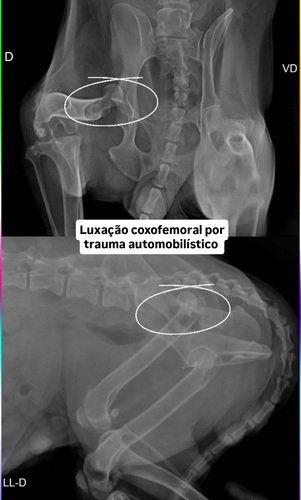

Os veterinários descobriram que eu tive uma luxação coxofemoral por trauma automobilístico.